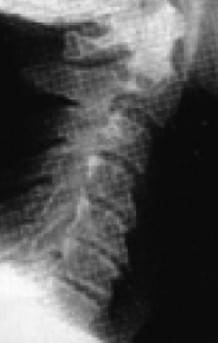

Причем, опять же, рост этого горбика она объясняет исключительно «солями» – остеохондрозом – и не связывает с изменившейся статикой своего позвоночника. В норме позвоночник, как известно, не должен быть прямым, как палка, а иметь физиологические изгибы. В частности, шейный отдел, состоящий из 7 позвонков, в норме должен быть чуть прогнутым внутрь (рис. 13).

Иллюстрация к книге — Биогимнастика для лица: система фейсмионика [i_017.jpg]

Рис. 13. Нормальная статика шейного отдела